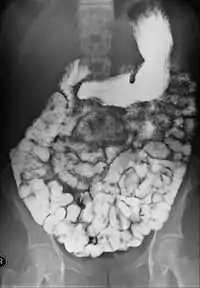

مركبات الباريوم (أيضاً من المواد المظللة الممتصة) ومثالها: سلفات الباريوم، والتي يتم حلها بالماء، ثم شربها، هذه المركبات لا تتحلل ولا يتم امتصاصها من قبل الأمعاء، مما يجعلها ملائمة لإظهار مجاري الجهاز الهضمي ومثالها ظاهر في الصورة. المواد المظللة من نوعية الباريوم تنشط حركة الأمعاء، هذه الخاصية تفسِّر استخدام هذه المواد أيضا كعلاج أو محاولة علاج الانسداد المعوي، وهناك فائدة أخرى، وهي إمكان مراقبة نتائج هذه المحاولة العلاجية باستخدام الأشعة.